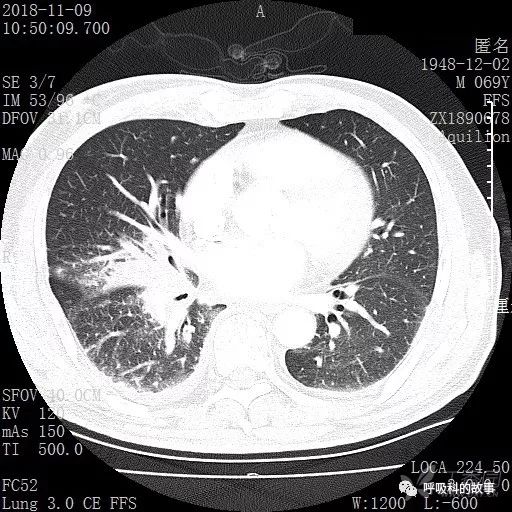

胸部增强CT示右肺门占位伴远端阻塞性肺炎,纵膈、右肺门、右侧颈根部、右侧腋下及肝门部肿大淋巴结。两侧胸腔少量积液。

纵隔窗的增强CT

肺窗CT